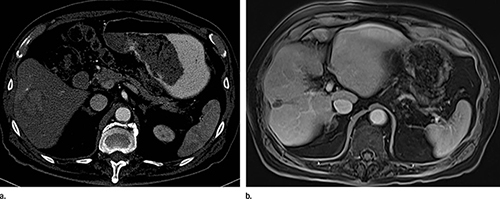

Images show (a) contrast material–enhanced CT scan before yttrium 90 of an 87-year-old man with 4-cm hepatocellular carcinoma in right lobe

Images show (a) contrast material–enhanced CT scan before yttrium 90 of an 87-year-old man with 4-cm hepatocellular carcinoma in right lobe. (b) Contrast-enhanced MR image at subsequent 9-year follow-up (now aged 96 years) shows complete necrosis.